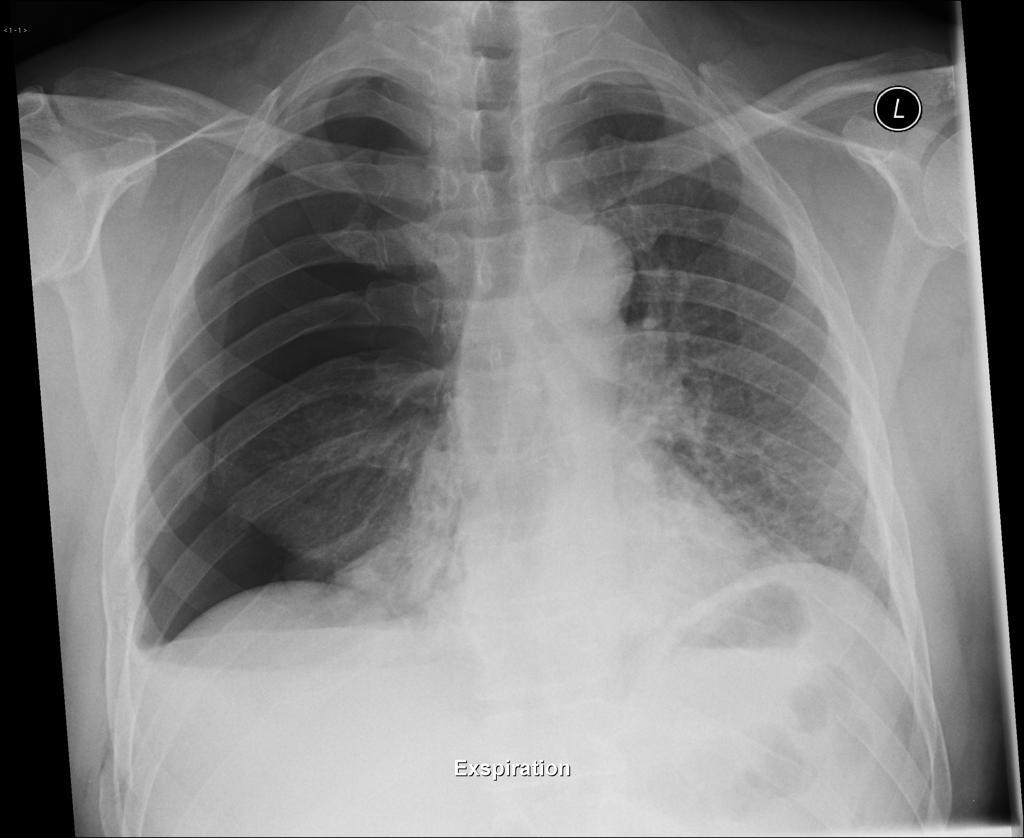

What is the main abnormality on this CXR and how do you know?

Tension pneumothorax

(with tracheal deviation)